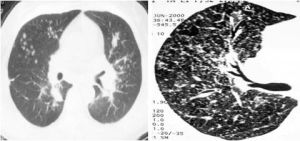

呼吸性細支氣管炎伴間質性肺病是一種非常少見的原因不明的間質性肺病。臨床主要表現為咳嗽和活動後呼吸困難;胸片表現為瀰漫性的網織影或結節狀的間質影,高分辨CT顯示模糊影;病理學特徵表現為在呼吸性細支氣管及其周圍的氣腔內有大量含色素的巨噬細胞聚集,肺泡間隔輕至中度的炎症和纖維化病變時相一致。在臨床表現和組織病理學上與脫屑性間質性肺炎不易區分。